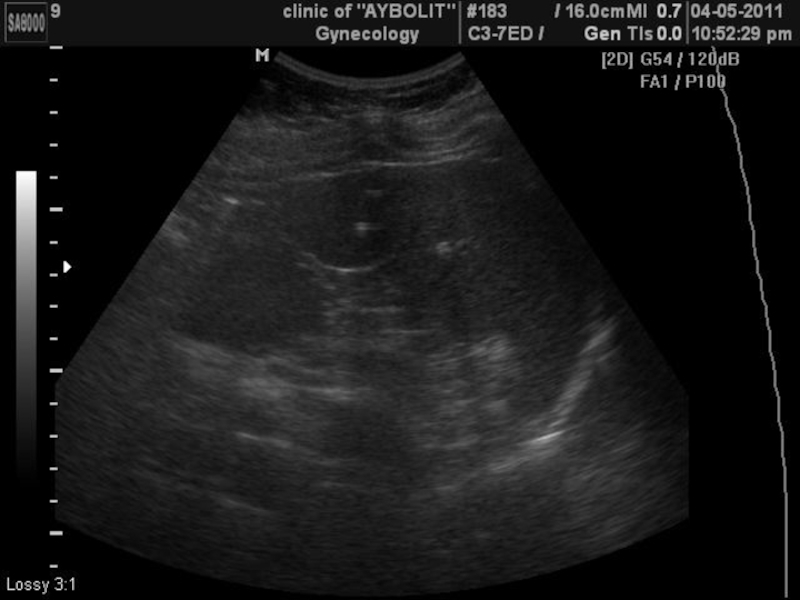

Слайд 6УЗИ печени

диагностируется гепатит, острый и хронический, жировая инфильтрация, цирроз, вторичные

изменения, являющиеся последствиями сердечных заболеваний, паразитарные кисты, доброкачественные (гемангиомы, кисты, аденомы,

кальцификаты) и злокачественные образования.

УЗИ печени диагностируется гепатит, острый и хронический, жировая инфильтрация, цирроз, вторичные изменения, являющиеся последствиями сердечных заболеваний, паразитарные кисты,